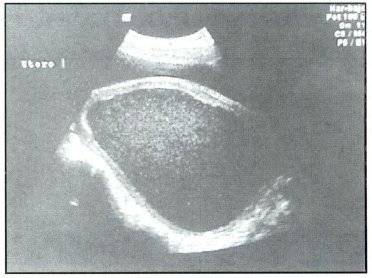

Fig: 1 Hematometra

La paciente es operada con el diagnóstico de tabique vaginal transverso incompleto a pesar de no demostrarse solución de continuidad en la vagina. Los reportes ecográficos y TAC reportaron hematometra gigante con hematocolpos y presencia de posible tabique vaginal en 1/3 inferior de vagina, que coincide con el examen físico que mostraba un tabique vaginal completo (Fig: 1,2,3,4).